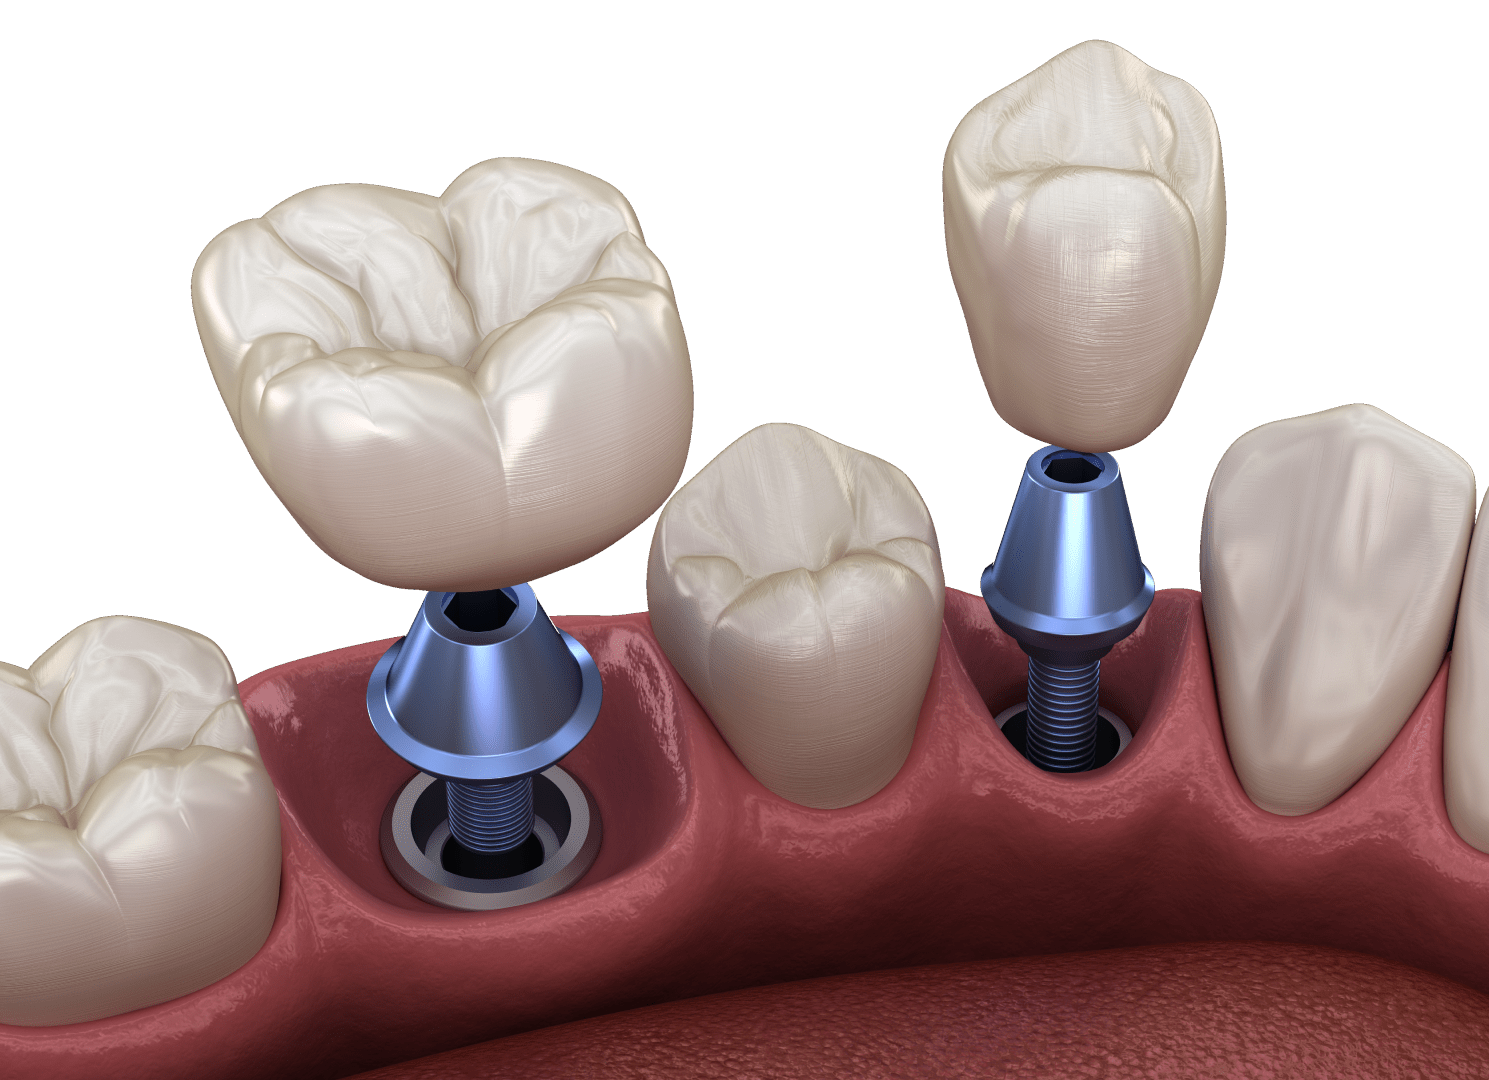

Імплантація зубів – найефективніший спосіб відновлення зубного ряду. Імпланти – міцні та довговічні вироби, які прослужать не один десяток років. Однак, вони підійдуть не для всіх пацієнтів. Протипоказання до імплантації зубів можуть бути абсолютними або мати тимчасовий характер. У першому разі пацієнтові пропонують альтернативу, а в другому — усунення несприятливого для імплантації фактору. І лише після цього можна братися за імпланти. Але все по порядку.

Будь-яка медична процедура (а тим більше хірургічна) має свої протипоказання. Імплантація не є винятком. Протипоказання до імплантації зубів бувають двох видів:

Як ви зрозуміли, абсолютні протипоказання до імплантації зубів порівняно рідкісні. Примітно, що список протипоказань до встановлення імплантів поступово скорочується завдяки впровадженню нових технологій. Розглянемо особливості імплантації за деяких поширених захворювань.